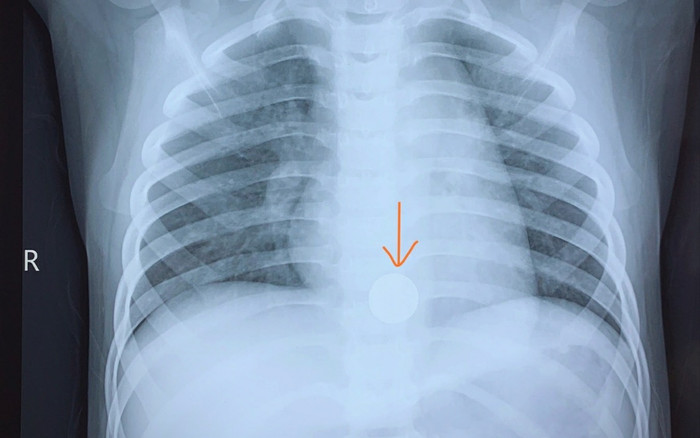

Dị vật pin cúc áo trong người bé trai 5 tuổi